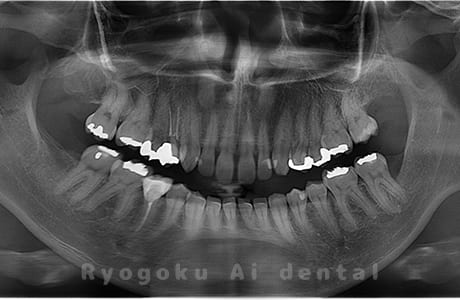

Case04

-

- 原因

- 上顎の親知らず、下顎の水平埋伏の親知らず

- 治療内容

- 上顎の親知らず、下顎の水平埋伏の親知らずを抜歯したケースです。

<リスク・副作用>

手術後は痛み、腫れ、痺れなどの副作用が生じる場合があります。